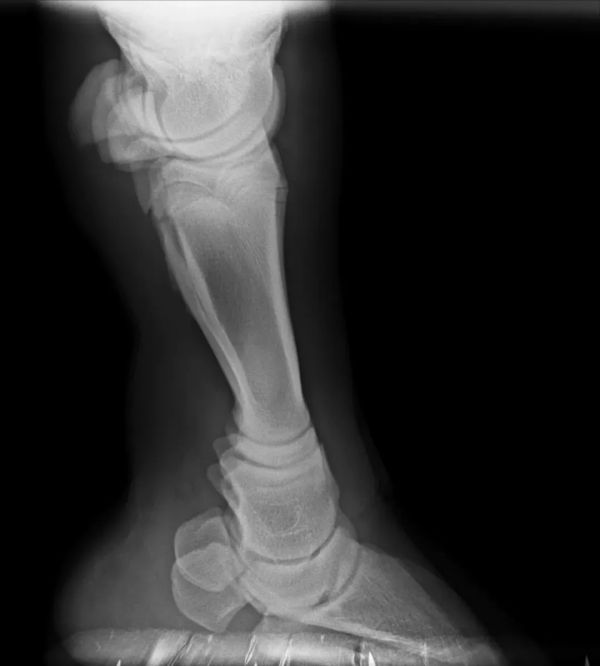

小七的蹄部X光

针对小七的具体情况,小七的右前蹄左右蹄甲不对称,右蹄甲有轻微变形,导致蹄甲缝变小。我们首先是使用锉刀沿着蹄甲缝进行精细的打磨,拓宽缝隙,让小七在行走时压力分布更加均匀,从而减少潜在的伤害风险。

通过这样的修整,小七的蹄部将能够更好地适应地面,不仅在行走时更加舒适,还能促进蹄甲的自然磨损,保持其健康和功能性。